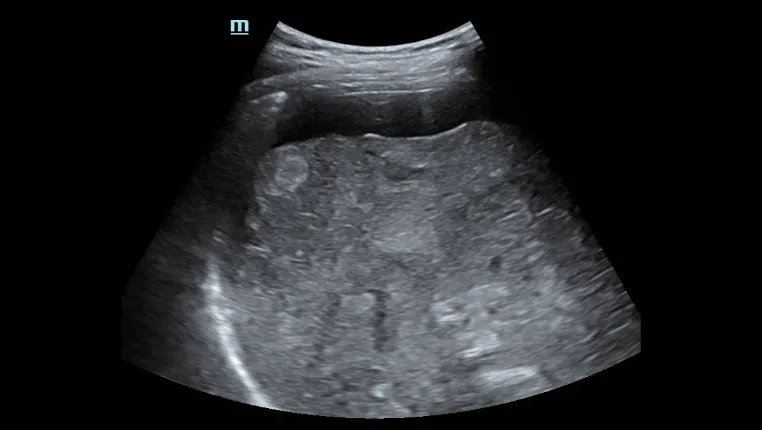

- Профессиональный ультразвуковой зонд для облегчения исследования асцита и т.д.

Асцит печени